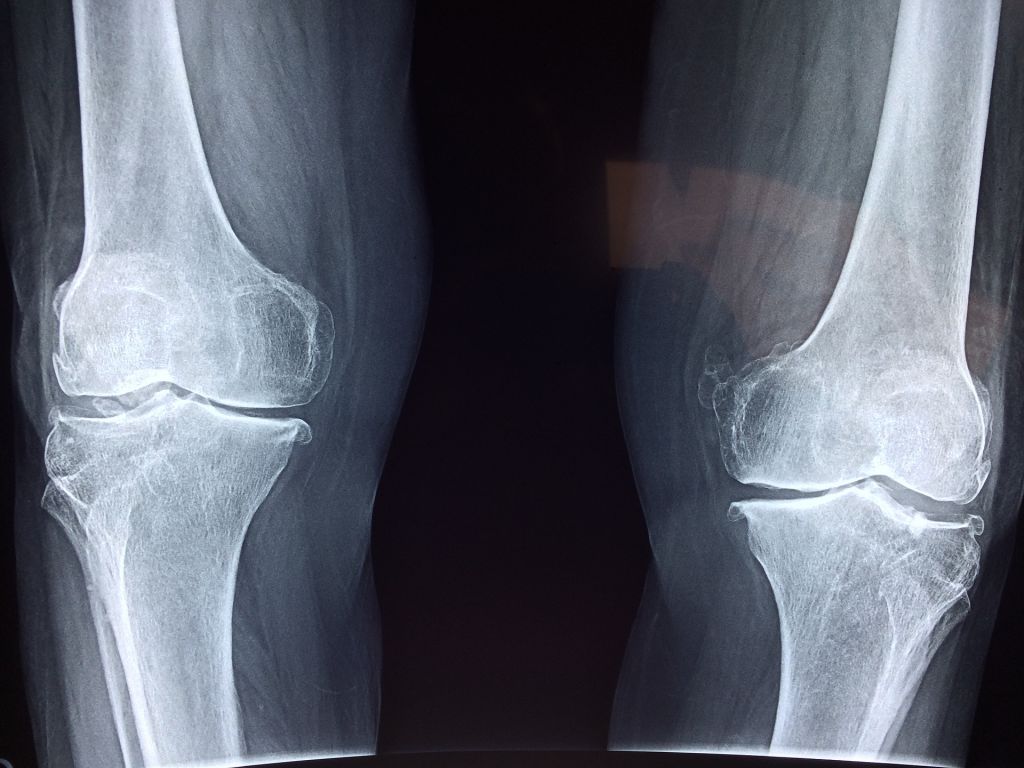

La leche de soja tiene muchos beneficios para la salud. En primer lugar, ayuda a prevenir la osteoporosis, aportando una buena dosis de calcio a los huesos. Incluso, suele recomendarse en el caso de mujeres postmenopáusicas y hombres mayores de 50 años precisamente para evitar trastornos óseos. También es muy buena para el corazón pues ayuda a reducir el colesterol y para el sistema circulatorio. Es muy nutritiva por su cantidad y calidad de proteínas. Y por último, como hemos dicho antes es un producto óptimo para las personas que tengan alergia a la proteína de la leche de vaca o a la lactosa pues pueden sustituirla por esta otra bebida.